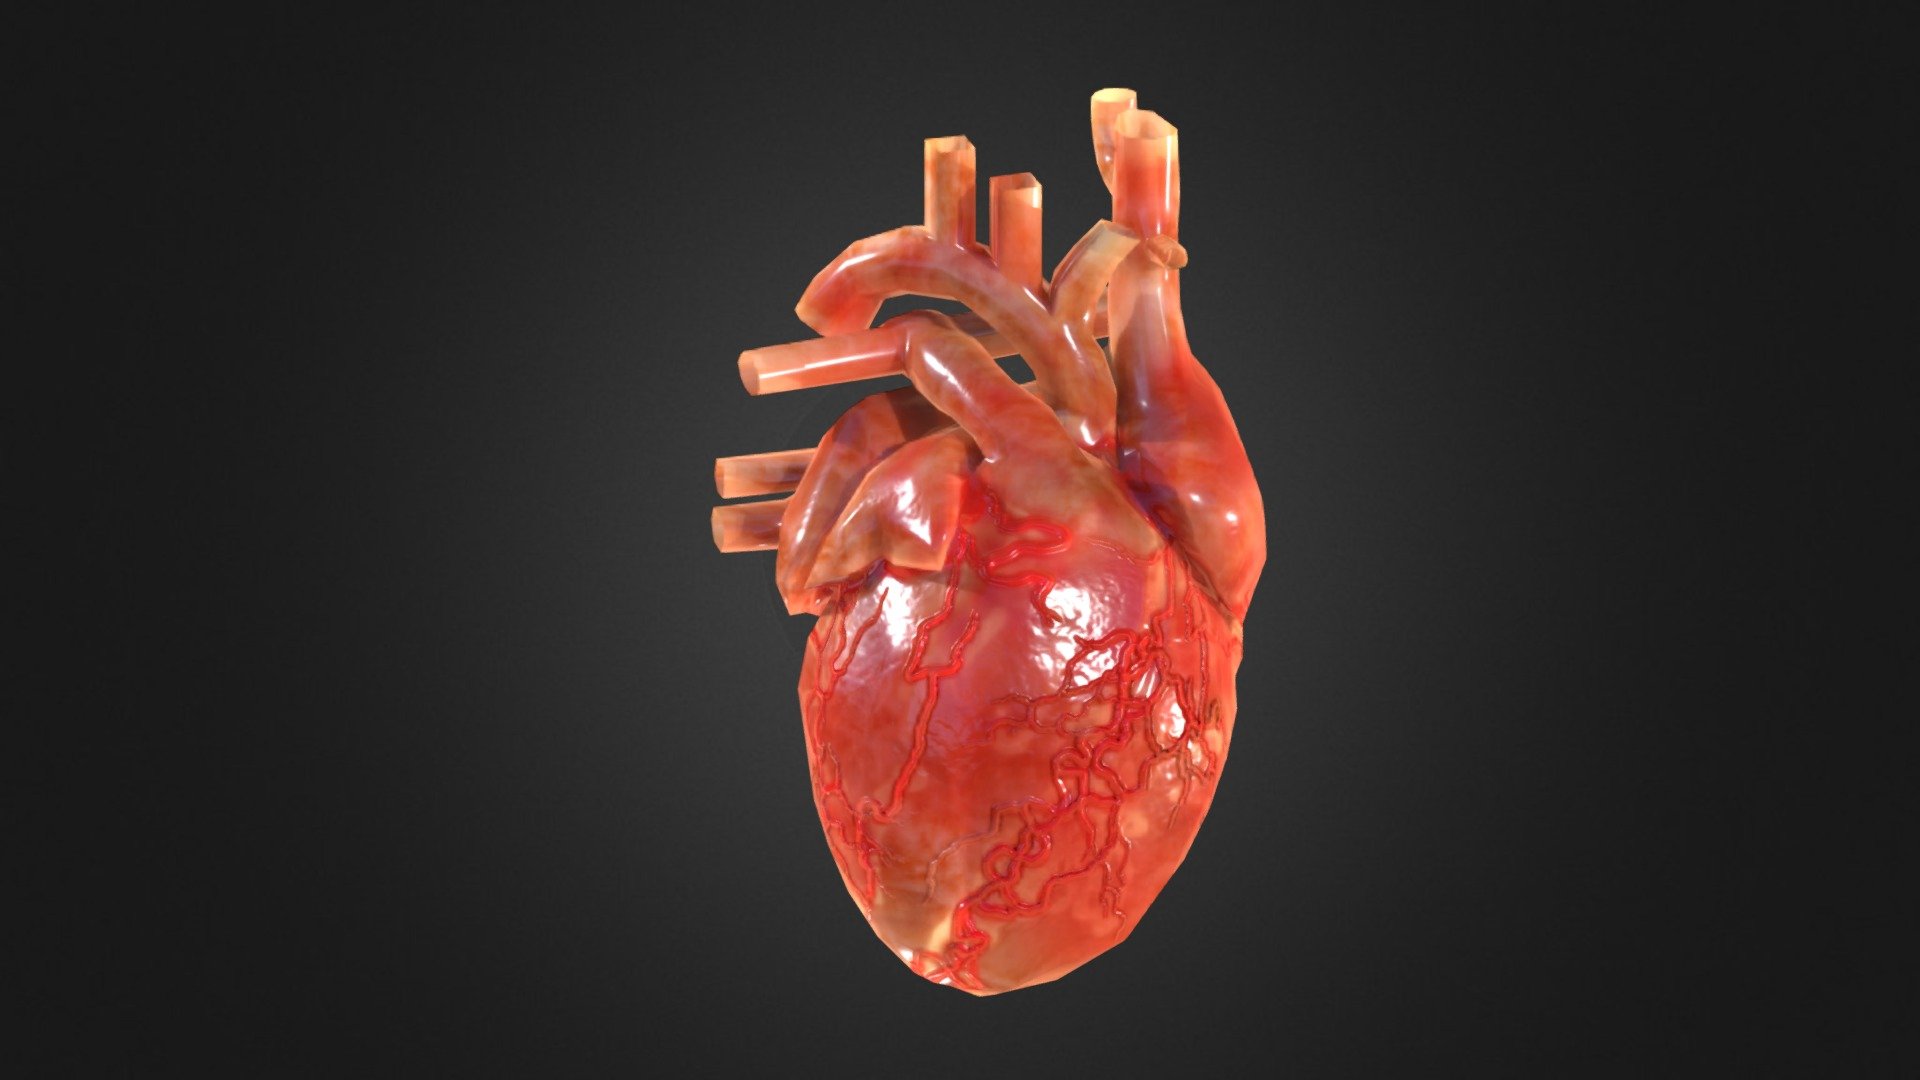

Анатомия здорового сердца: фотографии и иллюстрации